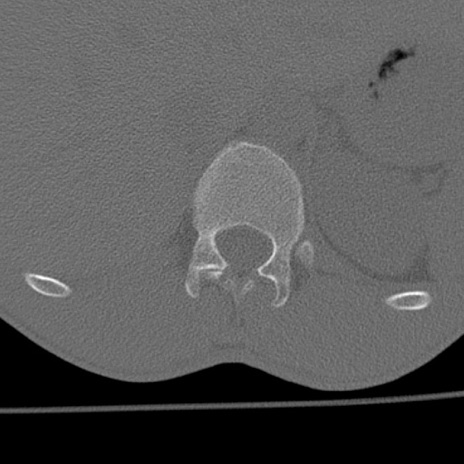

症例3 腰椎CT(横断像)

腰椎CT